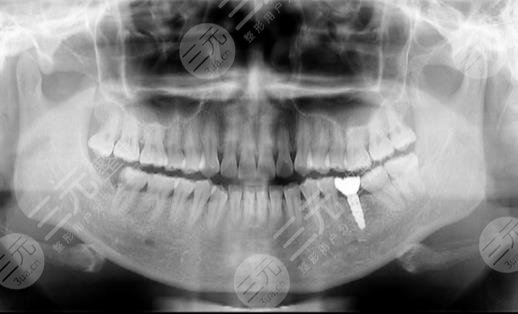

到医院进行面诊的时候,医生先让我咬了牙齿的模型,然后又拍了牙片,选择了牙齿的种植体,一星期之后,我来到了医院进行种植牙。整个种植牙的过程是很快的,而且因为打了局部mz也没有任何的感觉。大家现在可以看到我的种植牙是十分成功的,而且看上去十分的洁白,跟周围的牙齿形成了鲜明的对比。